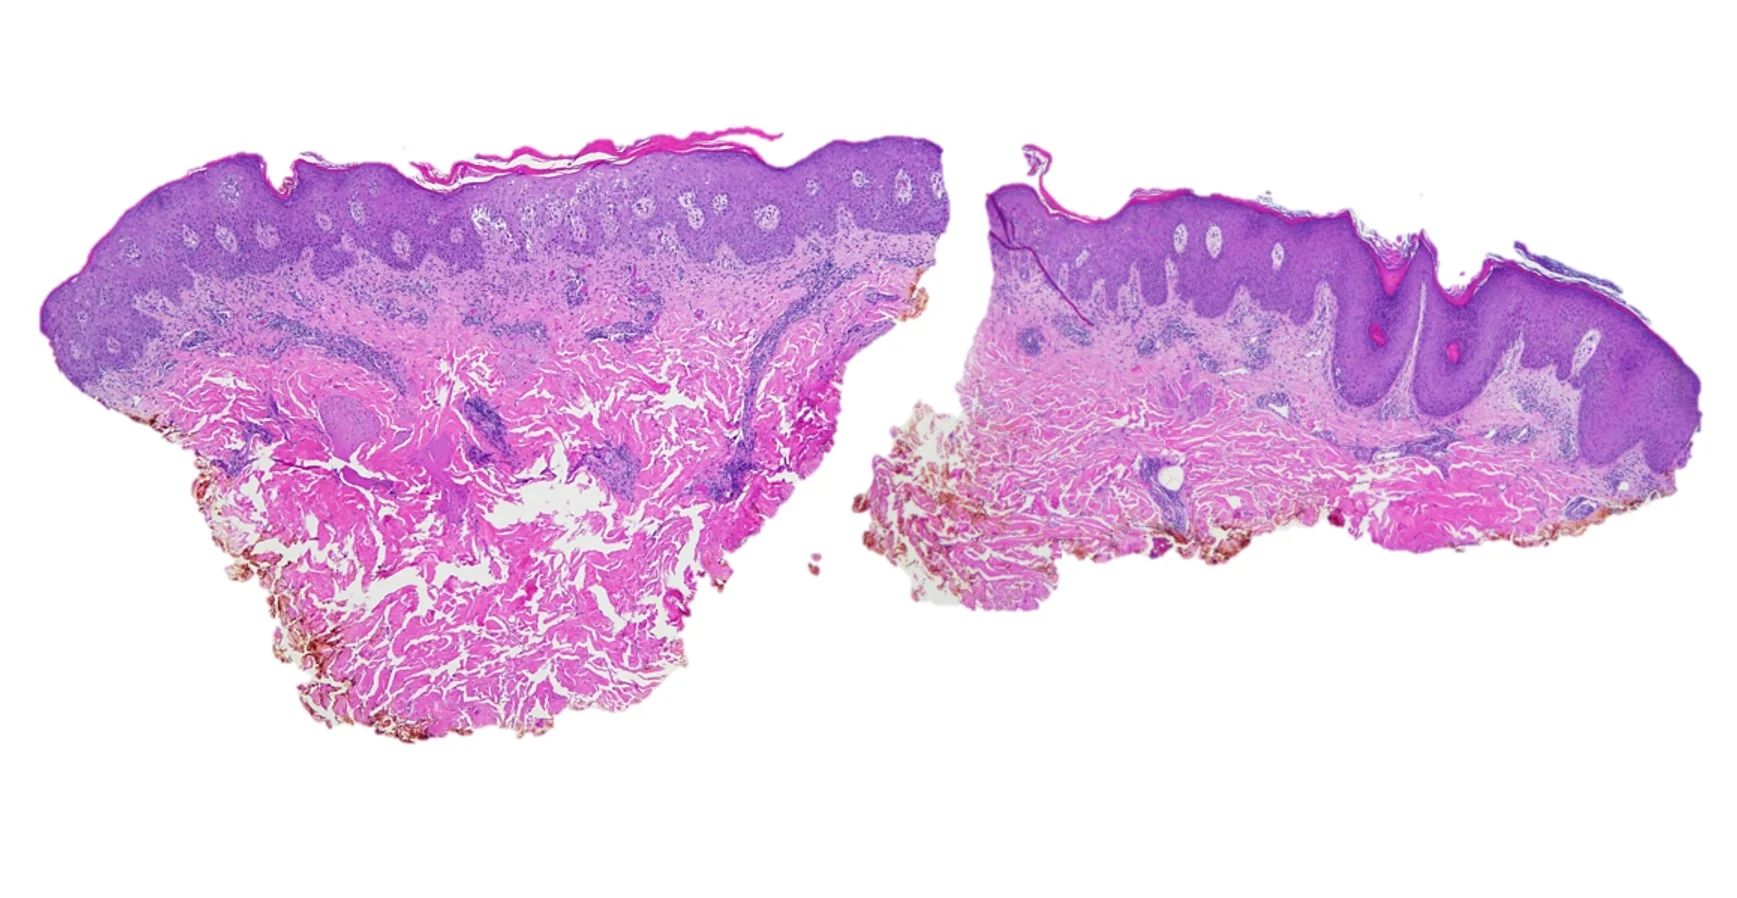

Case 1a: Secondary Syphilis

Histopathology: Skin with a neutrophilic infiltrate in the upper dermis accompanied by vascular dilation and dermal edema. Overlying epidermis with mild spongiosis and parakeratosis containing neutrophils. Focal neutrophilic pustules within the epidermis. An immunohistochemical study for treponema pallidum showed numerous spirochete organisms within the epidermis and at the dermal epidermal junction with scattered organisms in the papillary dermis. A PAS stain was negative for fungal elements.

Diagnosis: Secondary Syphilis

Case 1b: Granulomatous Syphilis

Histopathology: Superficial and deep inflammatory infiltrate consisting of lymphocytes, histiocytes, and plasma cells. Suppurative granulomatous inflammation was also seen, with scattered eosinophils and multinucleated giant cells. The infiltrate was predominantly perivascular and periadnexal and the epidermis was thinned with some areas of spongiosis and overlying crust. Special stains for PAS, FITE and Gram were negative. An immunohistochemical stain for T. pallidum confirmed the presence of spirochetes.

Diagnosis: Granulomatous syphilis

Point of Emphasis: Granulomatous syphilis is one of the less common but exuberant presentations of secondary syphilis. The histopathological appearance of secondary syphilis can be as varied as and just as challenging as its clinical presentation. It is considered one of the great “histopathological imitators”. The most common histologic presentation consists of a plasma cell-rich infiltrate with endothelial proliferation and swelling. However, psoriasiform, spongiotic, lichenoid, and perivascular patterns have also been described. No single histological finding is pathognomonic for this disease. Therefore, a high level of suspicion is essential whenever a dermal-based granulomatous infiltration is identified, especially in the setting of an increased number of plasma cells, even if slight. Mixed and multiple patterns of inflammation should also raise suspicion. Further studies, preferably immunohistochemistry for Treponema pallidum, should then be performed in order to exclude this entity.